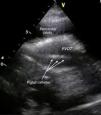

A 77-year-old woman presented to our emergency department with worsening shortness of breath. She was hemodynamically stable. Initial work-up was significant for hemoglobin 10.3 g/dl and enlarged cardiac silhouette on the chest X-ray. Transthoracic echocardiography showed a large circumferential pericardial effusion and dilated inferior vena cava. There was no right chamber collapse. Therapeutic pericardiocentesis was performed in the cardiac catheterization laboratory. An attempt was made to drain the pericardial fluid through a subxiphoid window under fluoroscopic guidance using a percutaneous needle. About 200 ml of serosanguinous fluid was aspirated. A guide wire was then advanced through the needle hub, the needle was removed and a pigtail catheter was introduced and left in place through a catheter-over-wire technique for further drainage. The procedure was considered successful by the performing cardiologist and the patient was admitted. No further drainage was noticed during the next 12 hours. The patient remained stable but did not report any improvement in her symptoms. Follow-up echocardiography 12 hours after the procedure showed massive pericardial effusion with dilated inferior vena cava. The catheter was seen in the right ventricle passing through the right ventricular free wall (Figures 1 and 2). Intravenous injection of agitated saline showed the catheter had advanced to the main pulmonary artery (Figure 3, Videos 1-3). Inadvertent right ventricular perforation and advancement of the pigtail catheter to the pulmonary artery was diagnosed and the patient required surgery for removal of the catheter and repair of the right ventricular free wall.